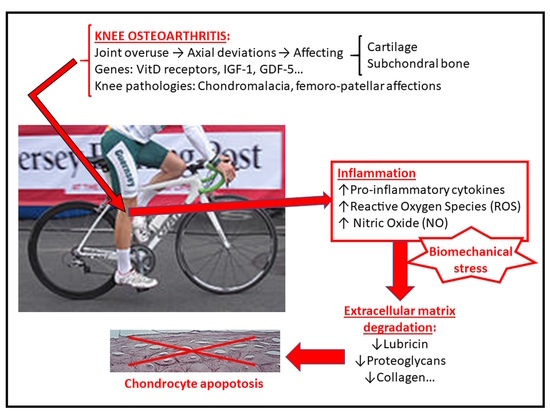

TKR I just want to ride my bike. Joint Replacement Patient sale, Mountain Biking after knee replacement Mountain Bike Reviews Forum sale, Who is running on a partial knee replacement Triathlon Forum sale, Knee Pain in Cyclists Bike Fit At Complete Physio sale, Should Knee Replacement Surgery Keep Riders Off the Bike Heck No sale, Above knee amputee Electric Bike Forums sale, Cycling With A Knee Replacement Ketones Sweet Spot Training Ask GCN Anything sale, FREE Community Health Forum Latest Advances in Total Joint sale, Knee Replacement Training Plan Returning to Cycling and Sport sale, TKR How much have your quads recovered Joint Replacement sale, Anyone with knee replacement and still mtn bikes Mountain Bike sale, When Can You Ride A Bike After A Total Knee Replacement Cycling sale, TKR Edema at 10 weeks Joint Replacement Patient Forum sale, Return to cycling after horrific knee injury Road Bike sale, Knee Replacement Training Plan One Year Post Op Report Chris sale, Why do my knees hurt Cycling knee pain explained and how to sale, How Cycling Helped This Man After Knee Replacement Surgery sale, The Prodigal Cyclist Joint Replacement Patient Forum sale, How to rehabilitate your total knee replacement using a bike sale, Knee Replacement Training Plan Returning to Cycling and Sport sale, Clinics and Practice Free Full Text Diagnostic Algorithm in sale, Photoshoot of the sale, Frontiers Simultaneous arthroscopic cystectomy and sale, Bike Riding After a Total Knee Replacement livestrong sale, Cycle magazine October November 2022 by Cycling UK Issuu sale, Why do my knees hurt Cycling knee pain explained and how to sale, JCM Free Full Text Inflammatory Process on Knee Osteoarthritis sale, What is a Total Knee Replacement What is a Total Knee sale, TKR I just want to ride my bike. Joint Replacement Patient sale, Spa Audax build photos Cycling UK Forum sale, Avid cyclist pedaling again after a partial knee replacement sale, How Cycling Helped This Man After Knee Replacement Surgery sale, When Recovery From Knee Surgery Hits a Wall Mackarey Mackarey PT sale, 4 Months after Total Knee Replacement Dr Sandeep Singh sale, Cycling post Total Knee Replacement When how Tips sale.

Knee replacement sale cycling forum